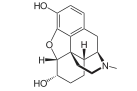

The pharmacodynamic response to an opioid depends upon the receptor to which it binds, its affinity for that receptor, and whether the opioid is an agonist or an antagonist. For example, the supraspinal analgesic properties of the opioid agonist morphine are mediated by activation of the μ1 receptor; respiratory depression and physical dependence by the μ2 receptor; and sedation and spinal analgesia by the κ receptor. Each group of opioid receptors elicits a distinct set of neurological responses, with the receptor subtypes (such as μ1 and μ2 for example) providing even more [measurably] specific responses. Unique to each opioid is its distinct binding affinity to the various classes of opioid receptors (e.g. the μ, κ, and δ opioid receptors are activated at different magnitudes according to the specific receptor binding affinities of the opioid). For example, the opiate alkaloid morphine exhibits high-affinity binding to the μ-opioid receptor, while ketazocine exhibits high affinity to ĸ receptors. It is this combinatorial mechanism that allows for such a wide class of opioids and molecular designs to exist, each with its own unique effect profile. Their individual molecular structure is also responsible for their different duration of action, whereby metabolic breakdown (such as N-dealkylation) is responsible for opioid metabolism.

Several semi-synthetic opioids were developed in Germany in the 1910s. The first, oxymorphone, was synthesized from thebaine, an opioid alkaloid in opium poppies, in 1914.[228] Next, Martin Freund and Edmund Speyer developed oxycodone, also from thebaine, at the University of Frankfurt in 1916.[229] In 1920, hydrocodone was prepared by Carl Mannich and Helene Löwenheim, deriving it from codeine. In 1924, hydromorphone was synthesized by adding hydrogen to morphine. Etorphine was synthesized in 1960, from the oripavine in opium poppy straw. Buprenorphine was discovered in 1972.[228]